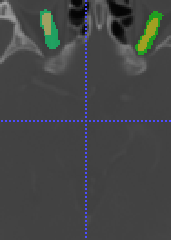

In Chapter 6, we propose an end-to-end, atlas-free 3D convolutional deep learning framework for fast and fully automated whole-volume HaN anatomy segmentation [115]. Our deep learning model, called AnatomyNet, segments OARs from head and neck CT images in an end-to-end fashion, receiving whole-volume HaN CT images as input and generating masks of all OARs of interest in one shot. AnatomyNet is built upon the popular 3D U-net architecture, but extends it in three important ways: 1) a new encoding scheme to allow auto-segmentation on whole-volume CT images instead of local patches or subsets of slices, 2) incorporating 3D squeeze-and-excitation residual blocks in encoding layers for better feature representation, and 3) a new loss function combining Dice scores and focal loss to facilitate the training of the neural model. These features are designed to address two main challenges in deep-learning-based HaN segmentation: a) segmenting small anatomies (i.e., optic chiasm and optic nerves) occupying only a few slices, and b) training with inconsistent data annotations with missing ground truth for some anatomical structures. We collect 261 HaN CT images to train AnatomyNet, and use MICCAI Head and Neck Auto Segmentation Challenge 2015 as a benchmark dataset to evaluate the performance of AnatomyNet. The objective is to segment nine anatomies: brain stem, chiasm, mandible, optic nerve left, optic nerve right, parotid gland left, parotid gland right, submandibular gland left, and submandibular gland right. Compared to previous state-of-the-art results from the MICCAI 2015 competition, AnatomyNet increases Dice similarity coefficient by 3.3% on average. AnatomyNet takes about 0.12 seconds to fully segment a head and neck CT image of dimension , significantly faster than previous methods. In addition, the model is able to process whole-volume CT images and delineate all OARs in one pass, requiring little pre- or post-processing. We demonstrate that our proposed model can improve segmentation accuracy and simplify the auto-segmentation pipeline. These contributions are released as an open-source software package called AnatomyNet, which is publicly available555https://github.com/wentaozhu/AnatomyNet-for-anatomical-segmentation. Portions of this chapter were published as part of [115].